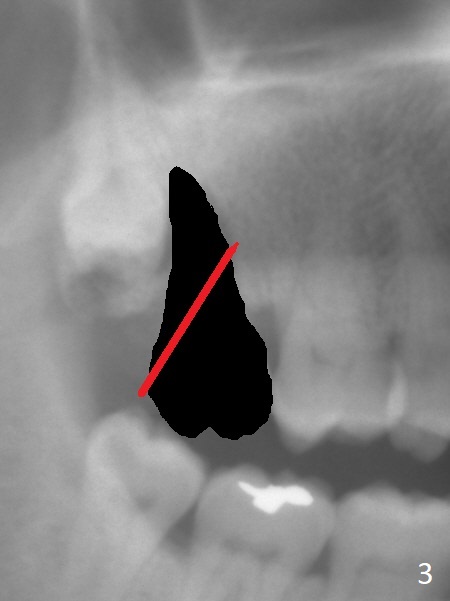

A 67-year-old man has pain associated with the tooth #2 with distal deep pockets (Fig.1), consistent with root fracture. The abnormal force may arise from the mesioangular lower 3rd molar (Fig.2 arrow). To avoid damage to the upper 3rd molar, osteotomy will be initiated obliquely with starter drill in the mesial slope of the socket (Fig.3 red). Once the starter drill makes a short entry, use 2 mm drill to change trajectory (Fig.4). Due to the uneven wall, an implant is expected to be placed distally by itself (Fig.5). The bone height is ~18 mm. If the patient agrees, remove the lower 3rd molar (Fig.5 black area).